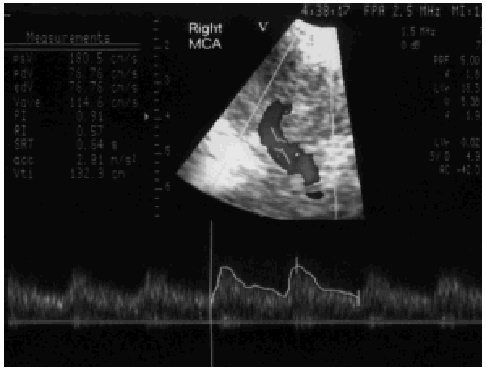

Ante la persistencia de valores elevados de la PIC se inició un tratamiento con manitol, con control inicial de la PIC de escasa duración. Tras precisar repetidas dosis por una nueva reelevación de la PIC y alcanzar valores de sodio plasmático de 154 mmol/l y osmolaridad en sangre de 327 mOsm/l, se decidió inducir un coma barbitúrico con tiopental con buen control posterior de la PIC (fig. 2).

Figura 2. Patrón sonográfico de arteria cerebral media derecha por Doppler transcraneal con codificación de color (DTCC) realizado tras tratamiento de HTEC durante 48 h con barbitúricos. Obsérvese el aumento de la velocidad diastólica hasta 76 cm/s y la disminución del índice de pulsatilidad (IP) de 0,91.

Pasadas 48 h con valores de PIC inferiores a 20 mmHg, se realizó nuevo control de DTCC que mostró desaparición del patrón restrictivo, por lo que el tiopental se retiró progresivamente sin producirse nuevo ascenso de la PIC.